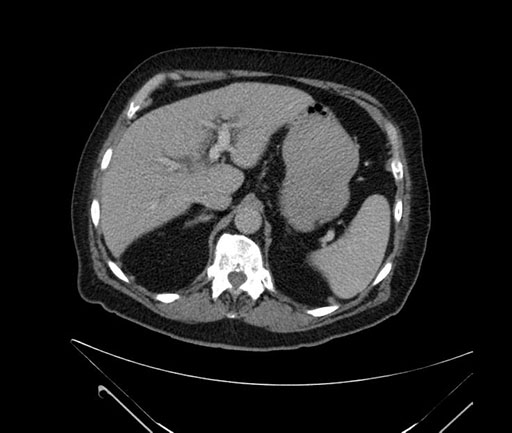

Whipple (pancreaticoduodenectomy) [case 7]

Axial - 3 months prior

Imaging analysis

Based on your CT findings, which issue(s) would give reason for "planned slowing down moment(s)" in this case?

Considering a standard Whipple procedure, what step(s) of the operation would you do differently in this case?